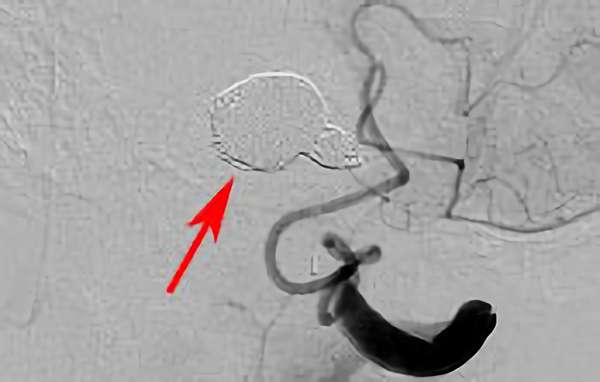

No.1618 手術後